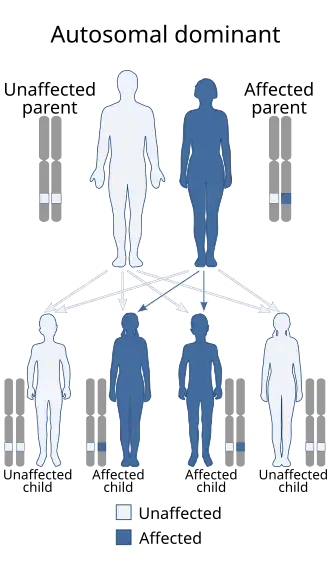

Waardenburg syndrome is caused by mutations in any of several genes that affect the operation of neural crest cells in embryonic development. Most types of Waardenburg syndrome are caused by autosomal dominant mutations. The few that are autosomal recessive are rare. In most cases, an affected person has inherited it from one parent with one of the dominant forms of the condition. A small percentage of cases result from spontaneous new mutations in the gene, where no family history of the condition exists.

- Type 3 is caused by a mutation in the gene PAX3, the same gene as in type 1.[2] It can be inherited in an autosomal dominant or autosomal recessive manner; it is possible for two parents with Waardenburg syndrome type 1 to have a child carrying both mutated copies of the PAX3 gene (25% chance) and present with Waardenburg syndrome type 3. A missense mutation has been documented to have this effect. However, it is also possible for Waardenburg syndrome type 3 to present spontaneously with just one mutated copy of PAX3. A deletion of the paired domain region of the gene has been documented to have this effect.[26][5] However, no major correlation has been found between type of mutation and disease severity. Severity tends to be dictated by mutations in other genes (epistasis), as evidenced by distinct familial patterns in severity not tied to Waardenburg mutation type.[5] Mutations in both copies of PAX3 have sometimes led to death before or shortly after birth, and mice with loss-of-function mutations in both copies of the gene do not survive.[5]